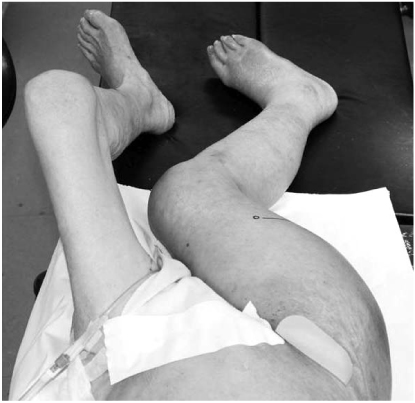

Fig. 4

(A) Digital subtraction angiography showing contrast extravasations originating from one of the minor proximal branch of right deep femoral artery, while filling a 2 cm sized pseudoaneurysm (arrow).

(B) After embolization. Postembolization angiography demonstrated no additional extravasation of contrast medium.

An 82-year-old woman, previously in bedridden state due to general weakness, was brought to the emergency department by guardians with right hip pain and severe thigh swelling. She was hospitalized at local hospital for 2 years and during stay, only sitting position was possible. Two weeks prior to our hospital visit, she had a history of fall-down from bed but was neglected. The radiographs demonstrated a subtrochanteric hip fracture (Seinsheimer classification grade 2b) with abrupt angulation of the proximal fragment and artherosclerotic vessel (Fig. 1). Additional findings included 30~40 degrees of flexion contracture of knee with severe swelling of the injured limb, more than twice the circumference compared to the contralateral limb (Fig. 2). There were ecchymoses in the anteromedial aspect of the right proximal thigh. The femoral and pedal pulses were symmetric and palpable in both lower limbs. On admission, the blood pressure was 100/80 mmHg with the heart rate of 90 bpm. The initial hemoglobin was 9.5 g/dl with the hematocrit of 0.22. The patient was managed with Buck's traction overnight. She was taken to the operating room the next day and gently placed on the fracture table under spinal anesthesia. The proximal fragment was severely abducted, externally rotated and flexed, making the nail entry into the greater trochanter difficult. Small (3 cm) incision at greater trochanter level was made in order to insert the reduction clamp. Large amount of hematoma was evacuated right after deep fascia incision. Reduction clamp was placed through an incision to reduce the proximal fragment prior to nailing. But, soon after the reduction against the deforming force, active bleeding was observed. The bleeding point was unidentifiable due to massive bleeding and inadequate operative field. Vital sign became unstable with systolic blood pressure dropping to 50 mmHg. Massive gauze packing on the suspected bleeding site was done with rapid intramedullary nail insertion (Proximal Femur Nail, Synthes, Davos, Switzerland). Skin closure and compressive dressing was performed to stabilize the vital sign. Popliteal and pedal pulse was weak. In order to identify the injured vessel, computed tomographic angiography was performed, and active bleeding in one of the branch vessel of right deep femoral artery was suspected (Fig. 3). To further evaluate the injured vessel, emergent digital subtraction angiography was performed. At first, the left common femoral artery was punctured by using a Seldinger technique. Extravasations of contrast medium was identified on the extremity angiogram, originating from one of the minor proximal branch of right deep femoral artery, while filling a 2 cm sized pseudoaneurysm (Fig. 4A). At this stage, coil embolization was attempted to stop the ongoing bleeding. The suspected branch of right deep femoral artery was superselected by using a 2.4 Fr microcatheter (Progreat, Terumo, Tokyo, Japan). Via the microcatheter, attempts were made to completely embolize the injured artery with 13 platinum-made microcoils (Tornado®, Cook Inc., Bloominton, Minnesota, USA), including four 6/2 mm, one 5/2 mm, six 4/2 mm and two 3/2 mm microcoils. Immediately after the embolization procedure, digital subtraction angiography was performed. The angiograms demonstrated complete occlusion of the feeding vessel and the cessation of the active bleeding (Fig. 4B). No other branch except the injured terminal branch was occluded on the angiogram. The day after embolization, the packed gauze was removed surgically.

Fig. 4 (A) Digital subtraction angiography showing contrast extravasations originating from one of the minor proximal branch of right deep femoral artery, while filling a 2 cm sized pseudoaneurysm (arrow). (B) After embolization. Postembolization angiography demonstrated no additional extravasation of contrast medium.